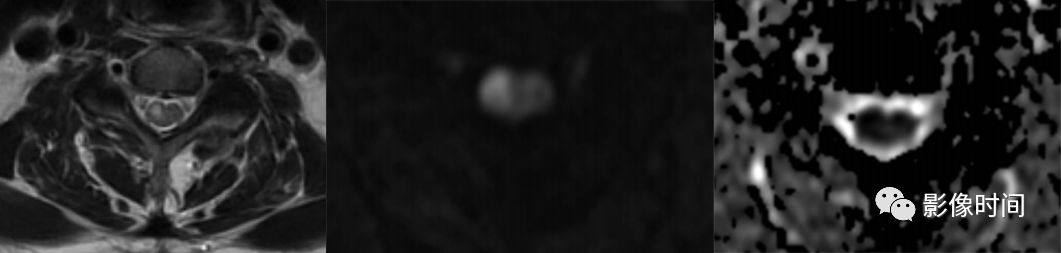

脊髓梗死(spinal infarction),各种原因(比如动脉夹层、椎体术后、纤维软骨栓塞等等)导致的脊髓供血动脉缺血,脊髓前动脉最多见

MRI:

前 2/3 脊髓(脊髓前动脉);双侧灰质前角(脊髓前动脉);后索(脊髓后动脉)

T2WI 高信号病灶,DWI 呈高信号,ADC 呈低信号

轴位「鹰眼征」

-

矢状位「铅笔征」

脊髓前动脉梗死导致双侧灰质前角梗死(鹰眼征),矢状位呈线样,DWI 提示细胞毒性水肿

脊髓前动脉梗死导致脊髓前 2/3 梗死,DWI 提示细胞毒性水肿

脊髓后动脉梗死导致脊髓后索梗死,DWI 提示细胞毒性水肿